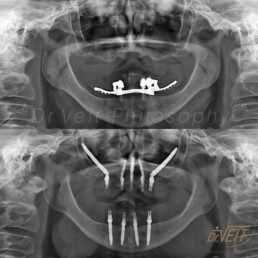

Arte de reabilitar os casos “impossíveis”. Pacientes que buscam a reabilitação oral podem conquistar um belo sorriso com segurança, mais conforto e tranquilidade com o uso do Implante Zigomático. A técnica possui o diferencial de realizar a implantação no osso zigomático e é indicada para casos de perda óssea maxilar avançada.